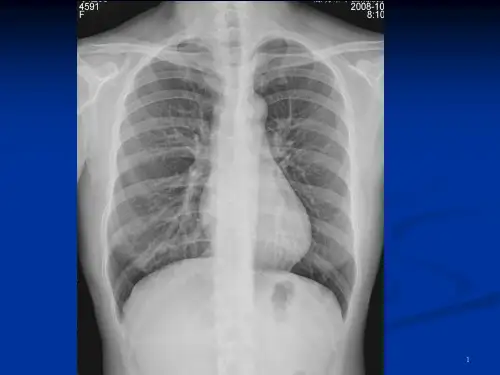

肺梗死阴影消退缓慢,需3~4周

2007-01-29

2007-04-11